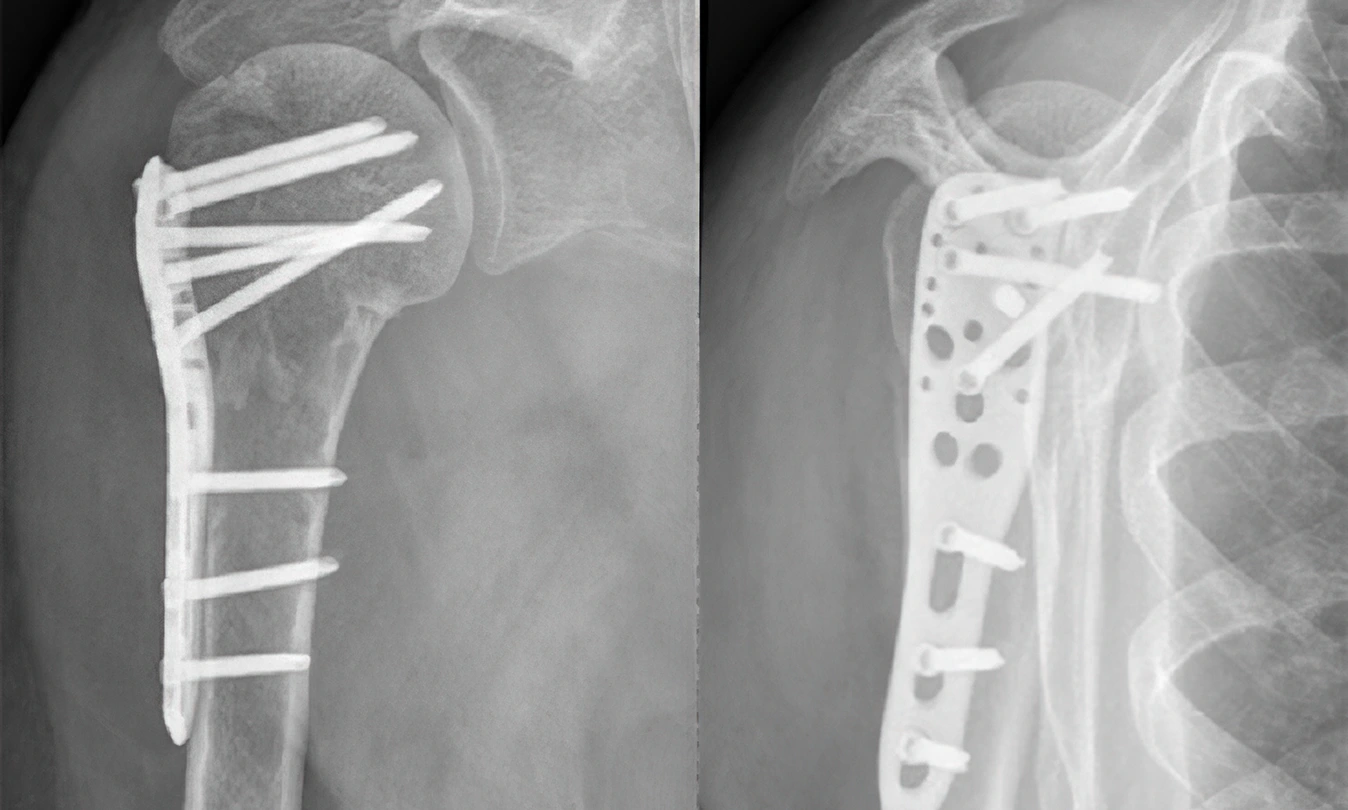

Operativno lečenje preloma ramena

Operativno lečenje ima za cilj da se polomljeni fragmenti dovedu u prvobitni položaj i stabilizuju. Uglavnom se primenjuje kod preloma gornjeg dela nadlaktice, pri čemu se stabilizacija najčešće sprovodi pločicom i šrafovima ili tzv. klinom. Ukoliko se, nakon što prelom sraste, ne dobije zadovoljavajući obim pokreta, preporučuje se vađenje pločice i tzv. release (popuštanje, oslobađanje od priraslica) ramena. Prelomi ramena, bez obzira na način tretiranja, često za posledicu imaju smanjenu pokretljivost ramena, a ponekad i bolove pri pokretima.

Osteosinteza preloma ramena, rendgenski snimak

Osteosinteza preloma ramena